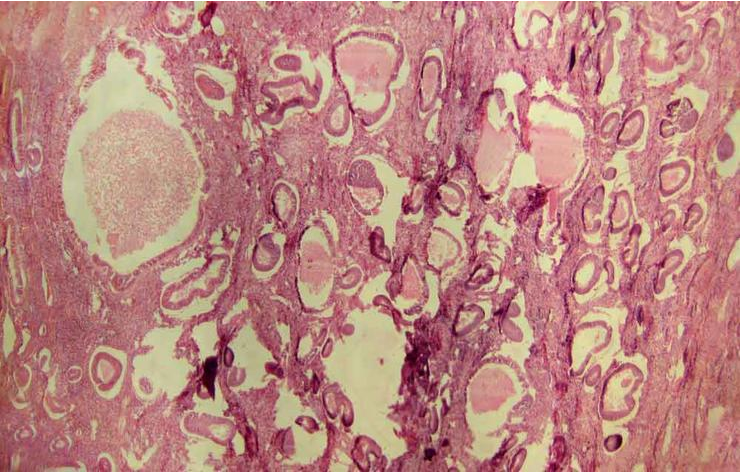

Đây là khối u nhỏ, lành tính (không phải ung thư) hình thành trong thành cơ của tử cung. Có tới 70% phụ nữ sẽ bị một hoặc nhiều khối u này trước tuổi 50, và chảy máu kinh nhiều là một trong những triệu chứng phổ biến của bênh này. Chảy máu nhỏ giọt ngoài kì kinh, chuột rút và đau bụng dưới cũng là triệu chứng. Phụ thuộc vào số lượng u xơ và vị trí, việc điều trị có thể là chăm sóc theo dõi hoặc cắt bỏ tử cung.